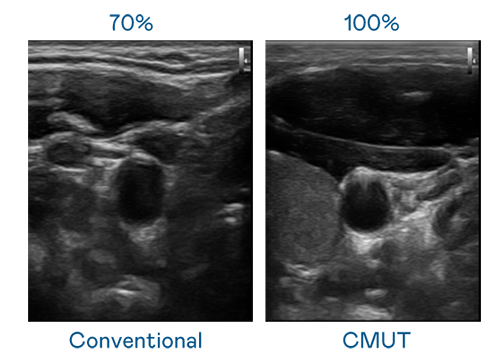

CMUT 技术是一种用电容式微机电元件来产生超音波讯号的技术。与传统 PZT 压电式技术相比,CMUT 频宽增加 30%,更宽频的超音波讯号让影像解析度大幅提升,是实现高影像品质医疗超音波扫描、促进精准医疗发展的关键技术。

大频宽带来超清晰影像

超音波影像的解析度高低,首先取决于探头能发出的讯号频宽。AG棋牌 CMUT 可提供高清晰的超音波讯号,提供高频宽、高灵敏度、影像纹理细节更高的超音波影像,协助医护人员缩短影像判读时间及利用精准的医疗影像进行诊断。